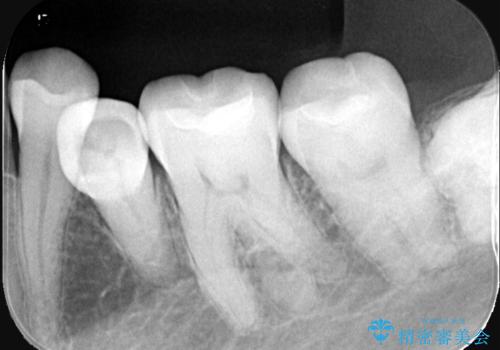

下顎大臼歯部に入っている保険適用のメタルインレーを、適合性と審美性の良いセラミックインレーでのやり替えとなりました。

メタルインレーを除去した際、古い裏層材やカリエスは除去し新たにCR裏層しています。